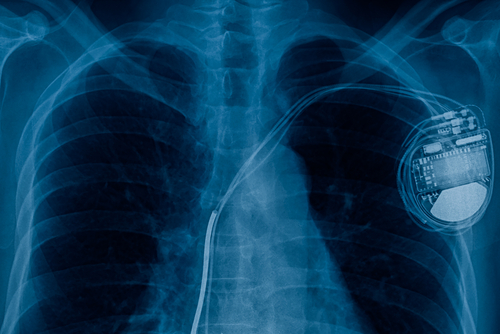

X-ray of a chest, which shows a pacemaker on the right-hand right of the chest cavity. As medical devices are an integral component of medical networks, their cyber security protection is imperative. This requires communication and coordination from all parties involved, including: